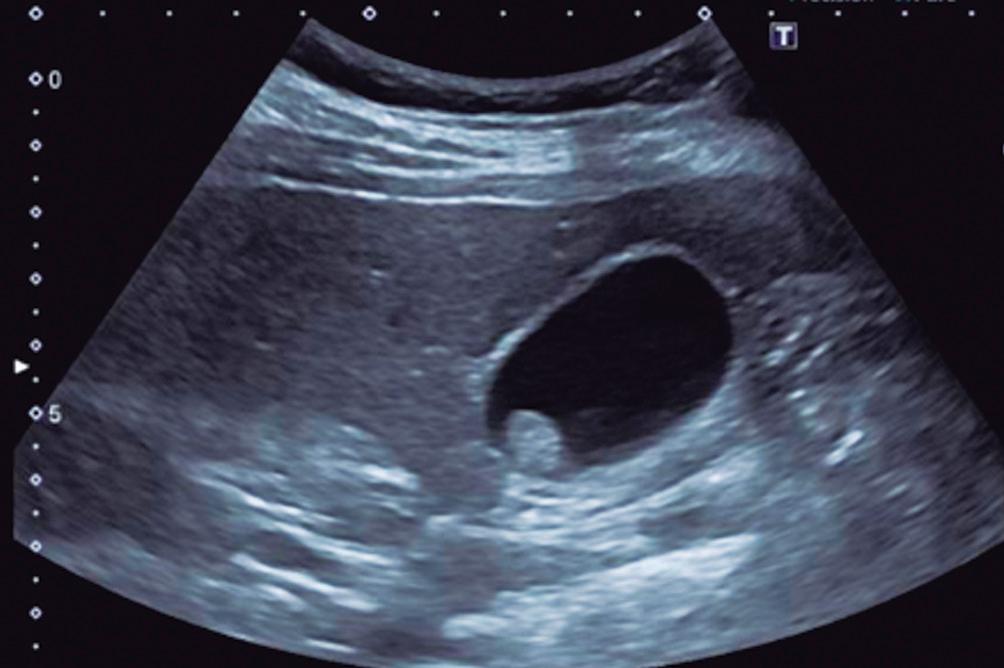

Hemangioma

El hemangioma es la lesión hepática benigna más frecuente (después de los quistes simples) y a menudo es múltiple. Es una lesión vascular benigna formada por estructuras vasculares inmersas en un estroma conectivo. Como casi todas las lesiones hepáticas, es irrigada mediante ramas de la arteria hepática, tiene flujo interno lento y carece de shunts arteriovenosos o de vasos de neoformación. Cuando los hemangiomas son de mayor tamaño suelen presentar una heterogeneidad central producto de la presencia de fibrosis, hialinización o trombosis. De dichas características surge el aspecto que presentan en las imágenes. En ecografía suelen ser hiperecogénicos (pueden ser también hipoecogenicos). Típicamente, tienen bordes netos y no presentan halo periférico; esta característica es sugestiva de lesiones malignas.

En la TC los hemangiomas son lesiones de bordes netos y frecuentemente de contornos lobulados. Al estar compuestas por vasos, su densidad es igual a la del pool sanguíneo, tanto en las imágenes sin contraste como en las diferentes fases de la evaluación poscontraste. El refuerzo es típicamente globular y progresivo, de forma centrípeta.

(Figura 1) En los hemangiomas de mayor tamaño el pasaje del contraste al centro de la lesión toma más tiempo e incluso no ocurre en aquellos más voluminosos.

A, en fase arterial; B, y en fase de equilibrio; C, que muestran una lesión de contornos lobulados y bordes netos en el lóbulo hepático derecho que presenta refuerzo globular, progresivo e isodenso con las estructuras vasculares.

Lesiones benignas localizadas en el hígado desde la mirada de las imágenes Mariano Volpacchio Figura 1. Hemangioma en tomografía computada. Imágenes axiales de la TC sin contraste Figura 2. Hemangioma en la RM. Imágenes axiales de la RM en secuencia T2 con supresión grasa con el refuerzo similar a las estructuras vasculares de aspecto globular y progresivo en sucesivas fases. Nótese la heterogeneidad del hemangioma de mayor tamaño en segmento VI. A B C